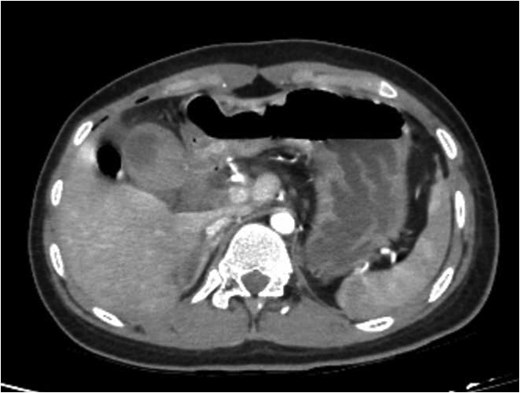

A 16-year-old female patient fell from the third floor of a secondary school building and was admitted to the Emergency Department with traumatic shock, and multiple organ injuries including a head injury, spinal fracture, femur fracture, and blunt abdominal trauma after the accident 1 h. The patient was hemodynamically unstable (body temperature 37°C; heart rate 120/min; blood pressure 80/50 mmHg; respiration: 22 beats/min). Her physical exam revealed traumatic shock with right upper quadrant abdominal tenderness. Bloodwork revealed an elevated white blood cell count at 14 700 cells/μL, low hemoglobin at 9.0 g/dL, abnormal prothrombin time test result (PT 42%/INR 1.91%) and elevated liver enzymes with alanine aminotransferase (ALT) at 144 U/L, aspartate aminotransferase (AST) at 427 U/L. Her past medical and surgical history were unremarkable. She had no home medications or any allergies. The patient had received initial first aid and secondary surveys such as broken bones fixed with cast immobilization, pain relief, blood transfusion, and focused assessment with sonography in trauma (FAST). The ultrasound found gallbladder wall thickening, suspected intra-gallbladder hematoma with free fluid collection in the Morison’s pouch, and no accompanying liver or splenic injury. After recovery from shock, computed tomography (CT) with intravenous contrast showed a thick-walled gallbladder with some pericholecystic fluid, free abdominal air bubbles, no contrast extravasation, and no evidence of accompanied liver or splenic trauma (Fig. 1).

CT showing thick-walled gallbladder with some pericholecystic fluid, free abdominal air bubbles.